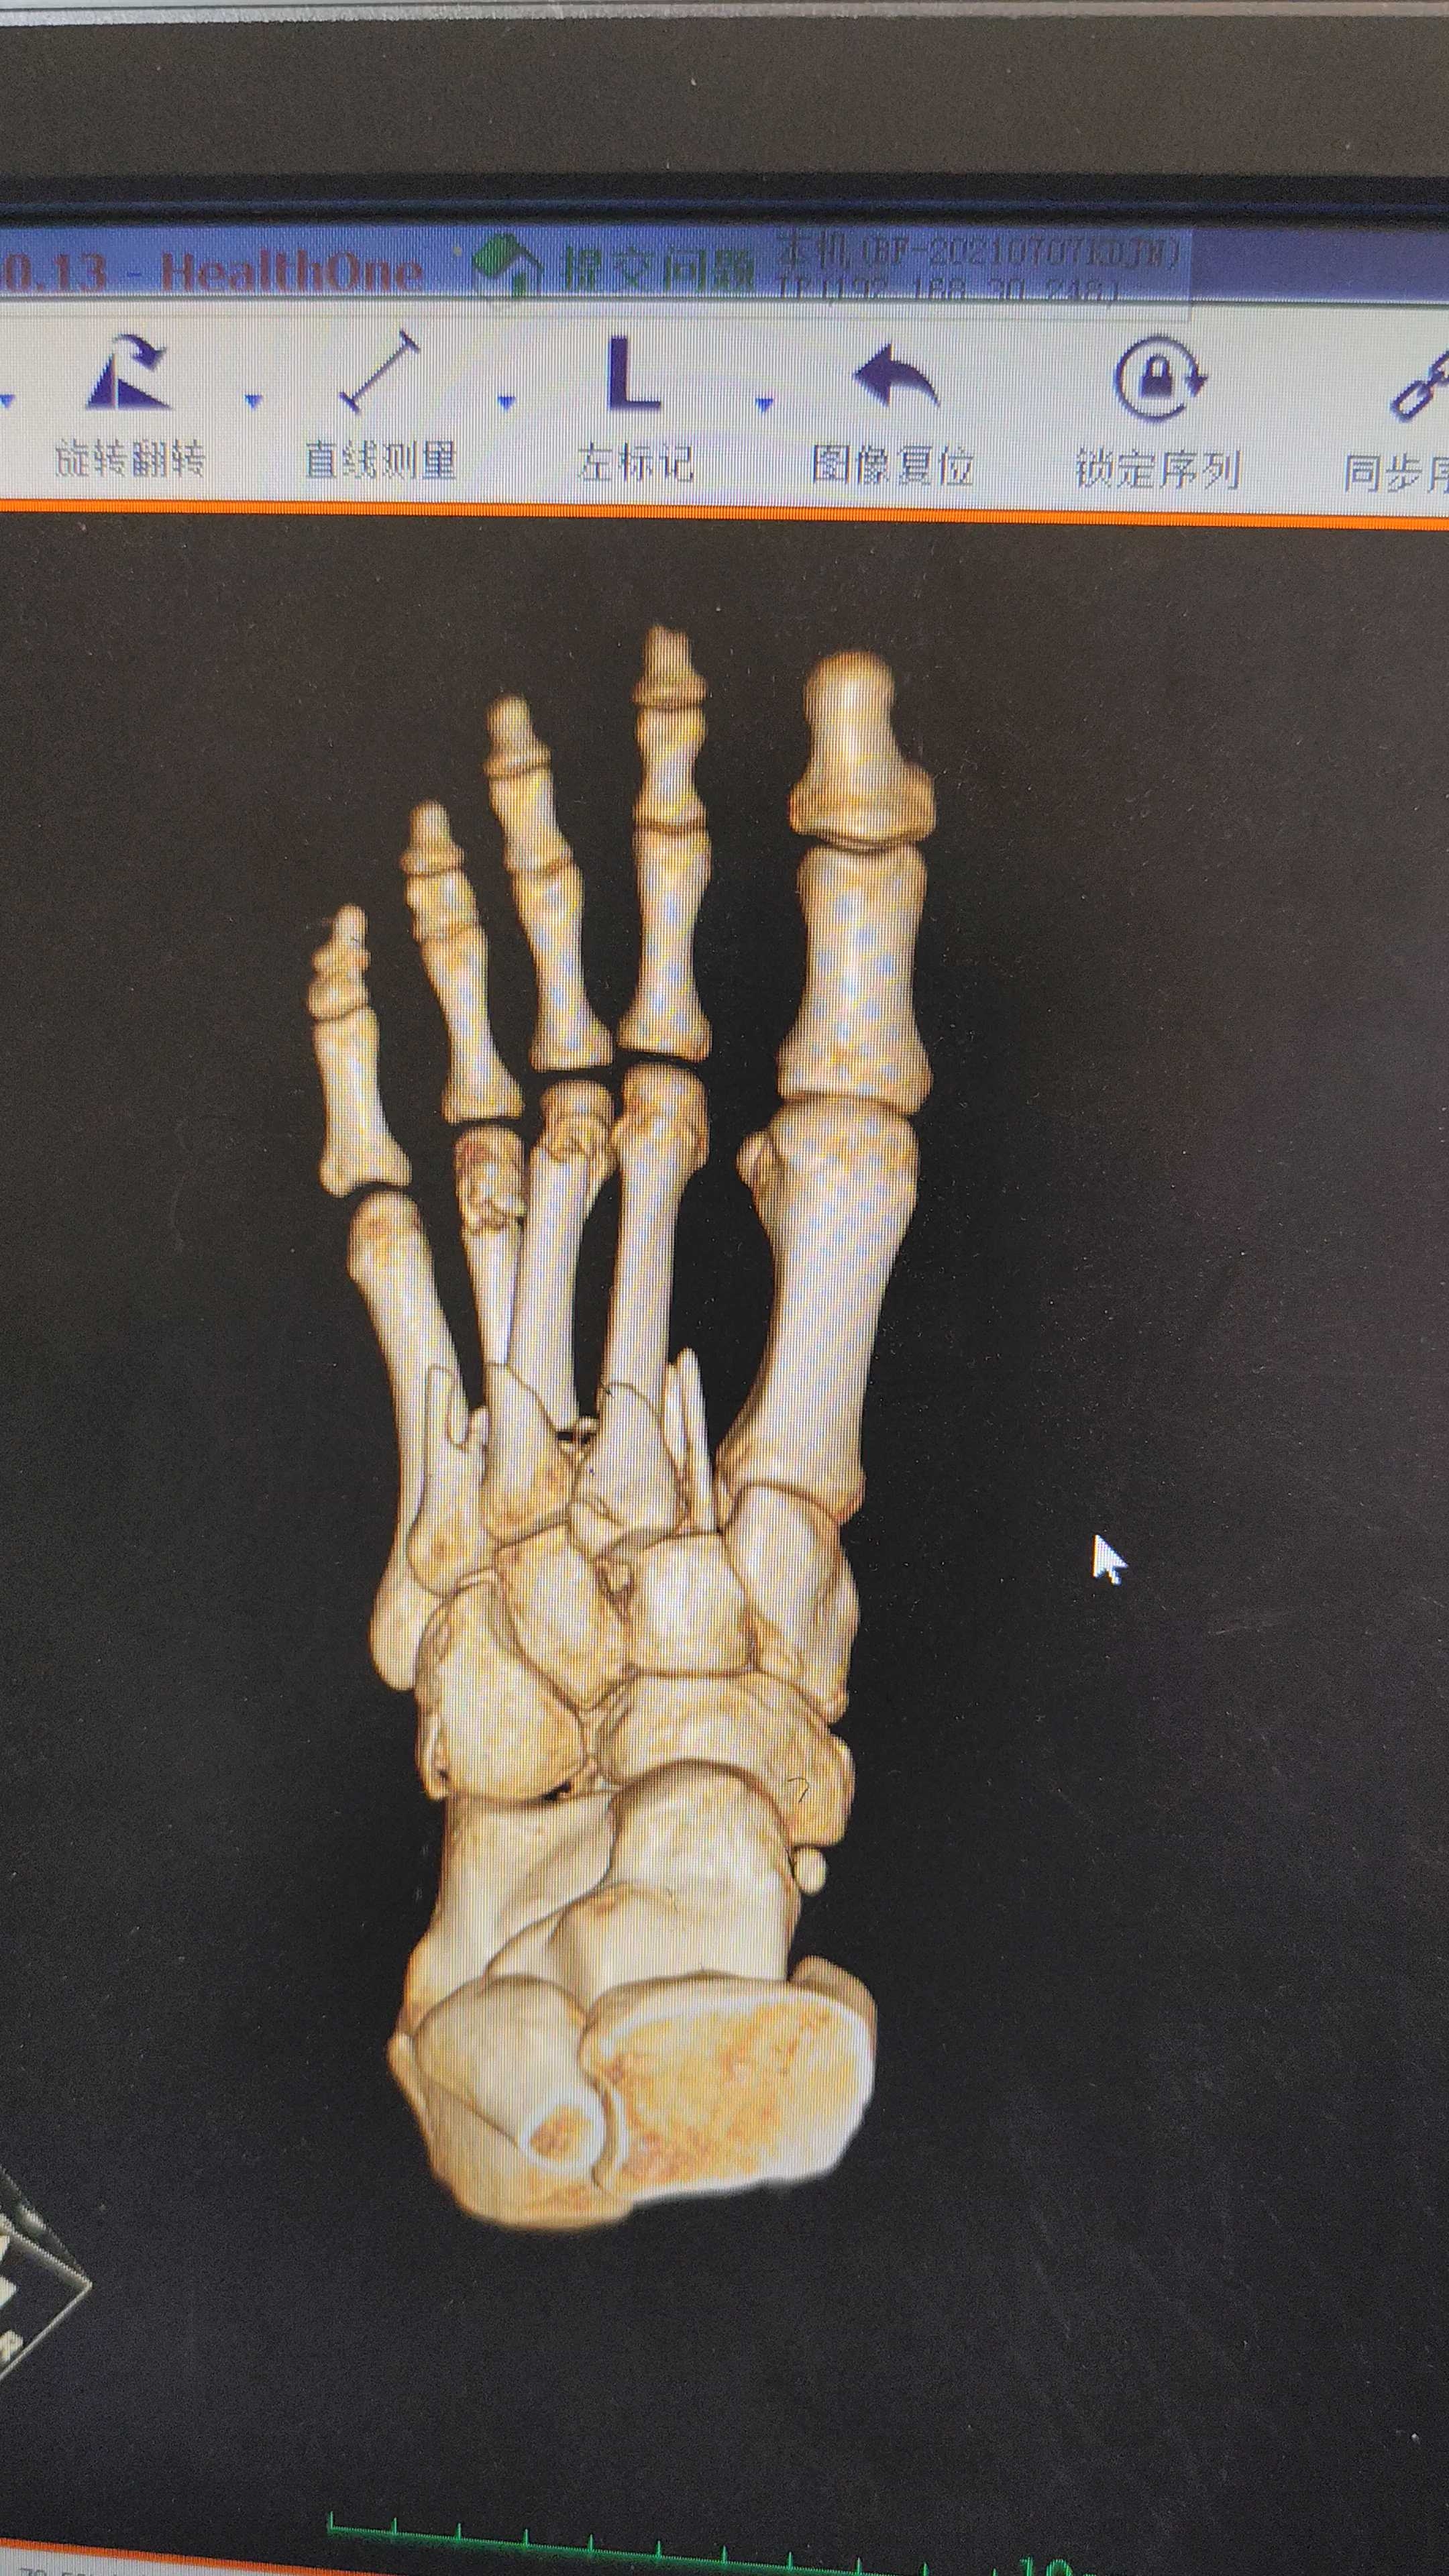

低能量lisfranc损伤的微创治疗.诊断:低能量lisfr - 抖音

右足第二跖骨基底楔骨骨折并lisfranc损伤的治疗过程